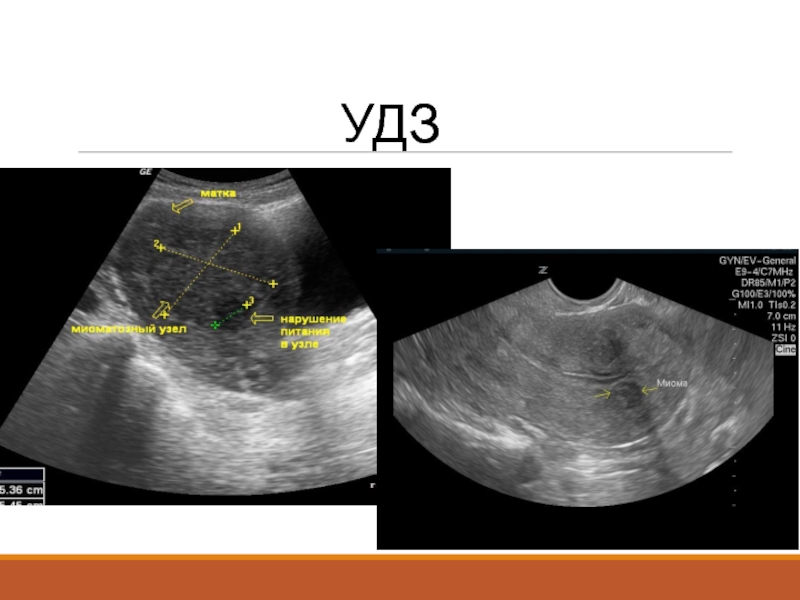

Слайд 21Диагностика әдістері

Анамнез жинау;

Гинекологиялық тексерулер;

УДЗ;

КТ;

МРТ;

Диагностикалық лапароскопия

Диагностика әдістеріАнамнез жинау;Гинекологиялық тексерулер;УДЗ;КТ;МРТ;Диагностикалық лапароскопия